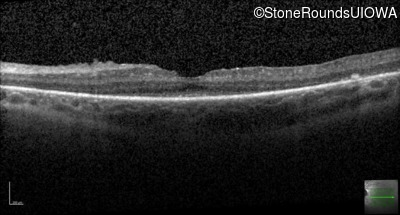

Optical Coherence Tomography - Left - 20/40

Exemplar / OCT Stack